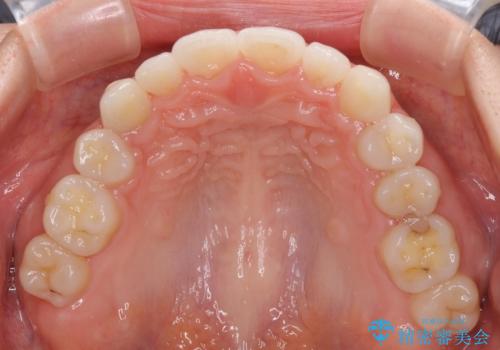

- ハーフリンガル

- 前歯のデコボコや八重歯、舌癖による開咬を気にして来院された患者様です。

目立たない装置を希望されたので、上顎が裏側装置のハーフリンガルを選択し、上顎小臼歯1本を抜歯して、補助装置を併用して矯正治療を行うこととしました。

補助装置を事前に使用したことで、あっという間に八重歯が改善し、ハーフリンガルにしては1年半もかからずに治療を終えることができました。